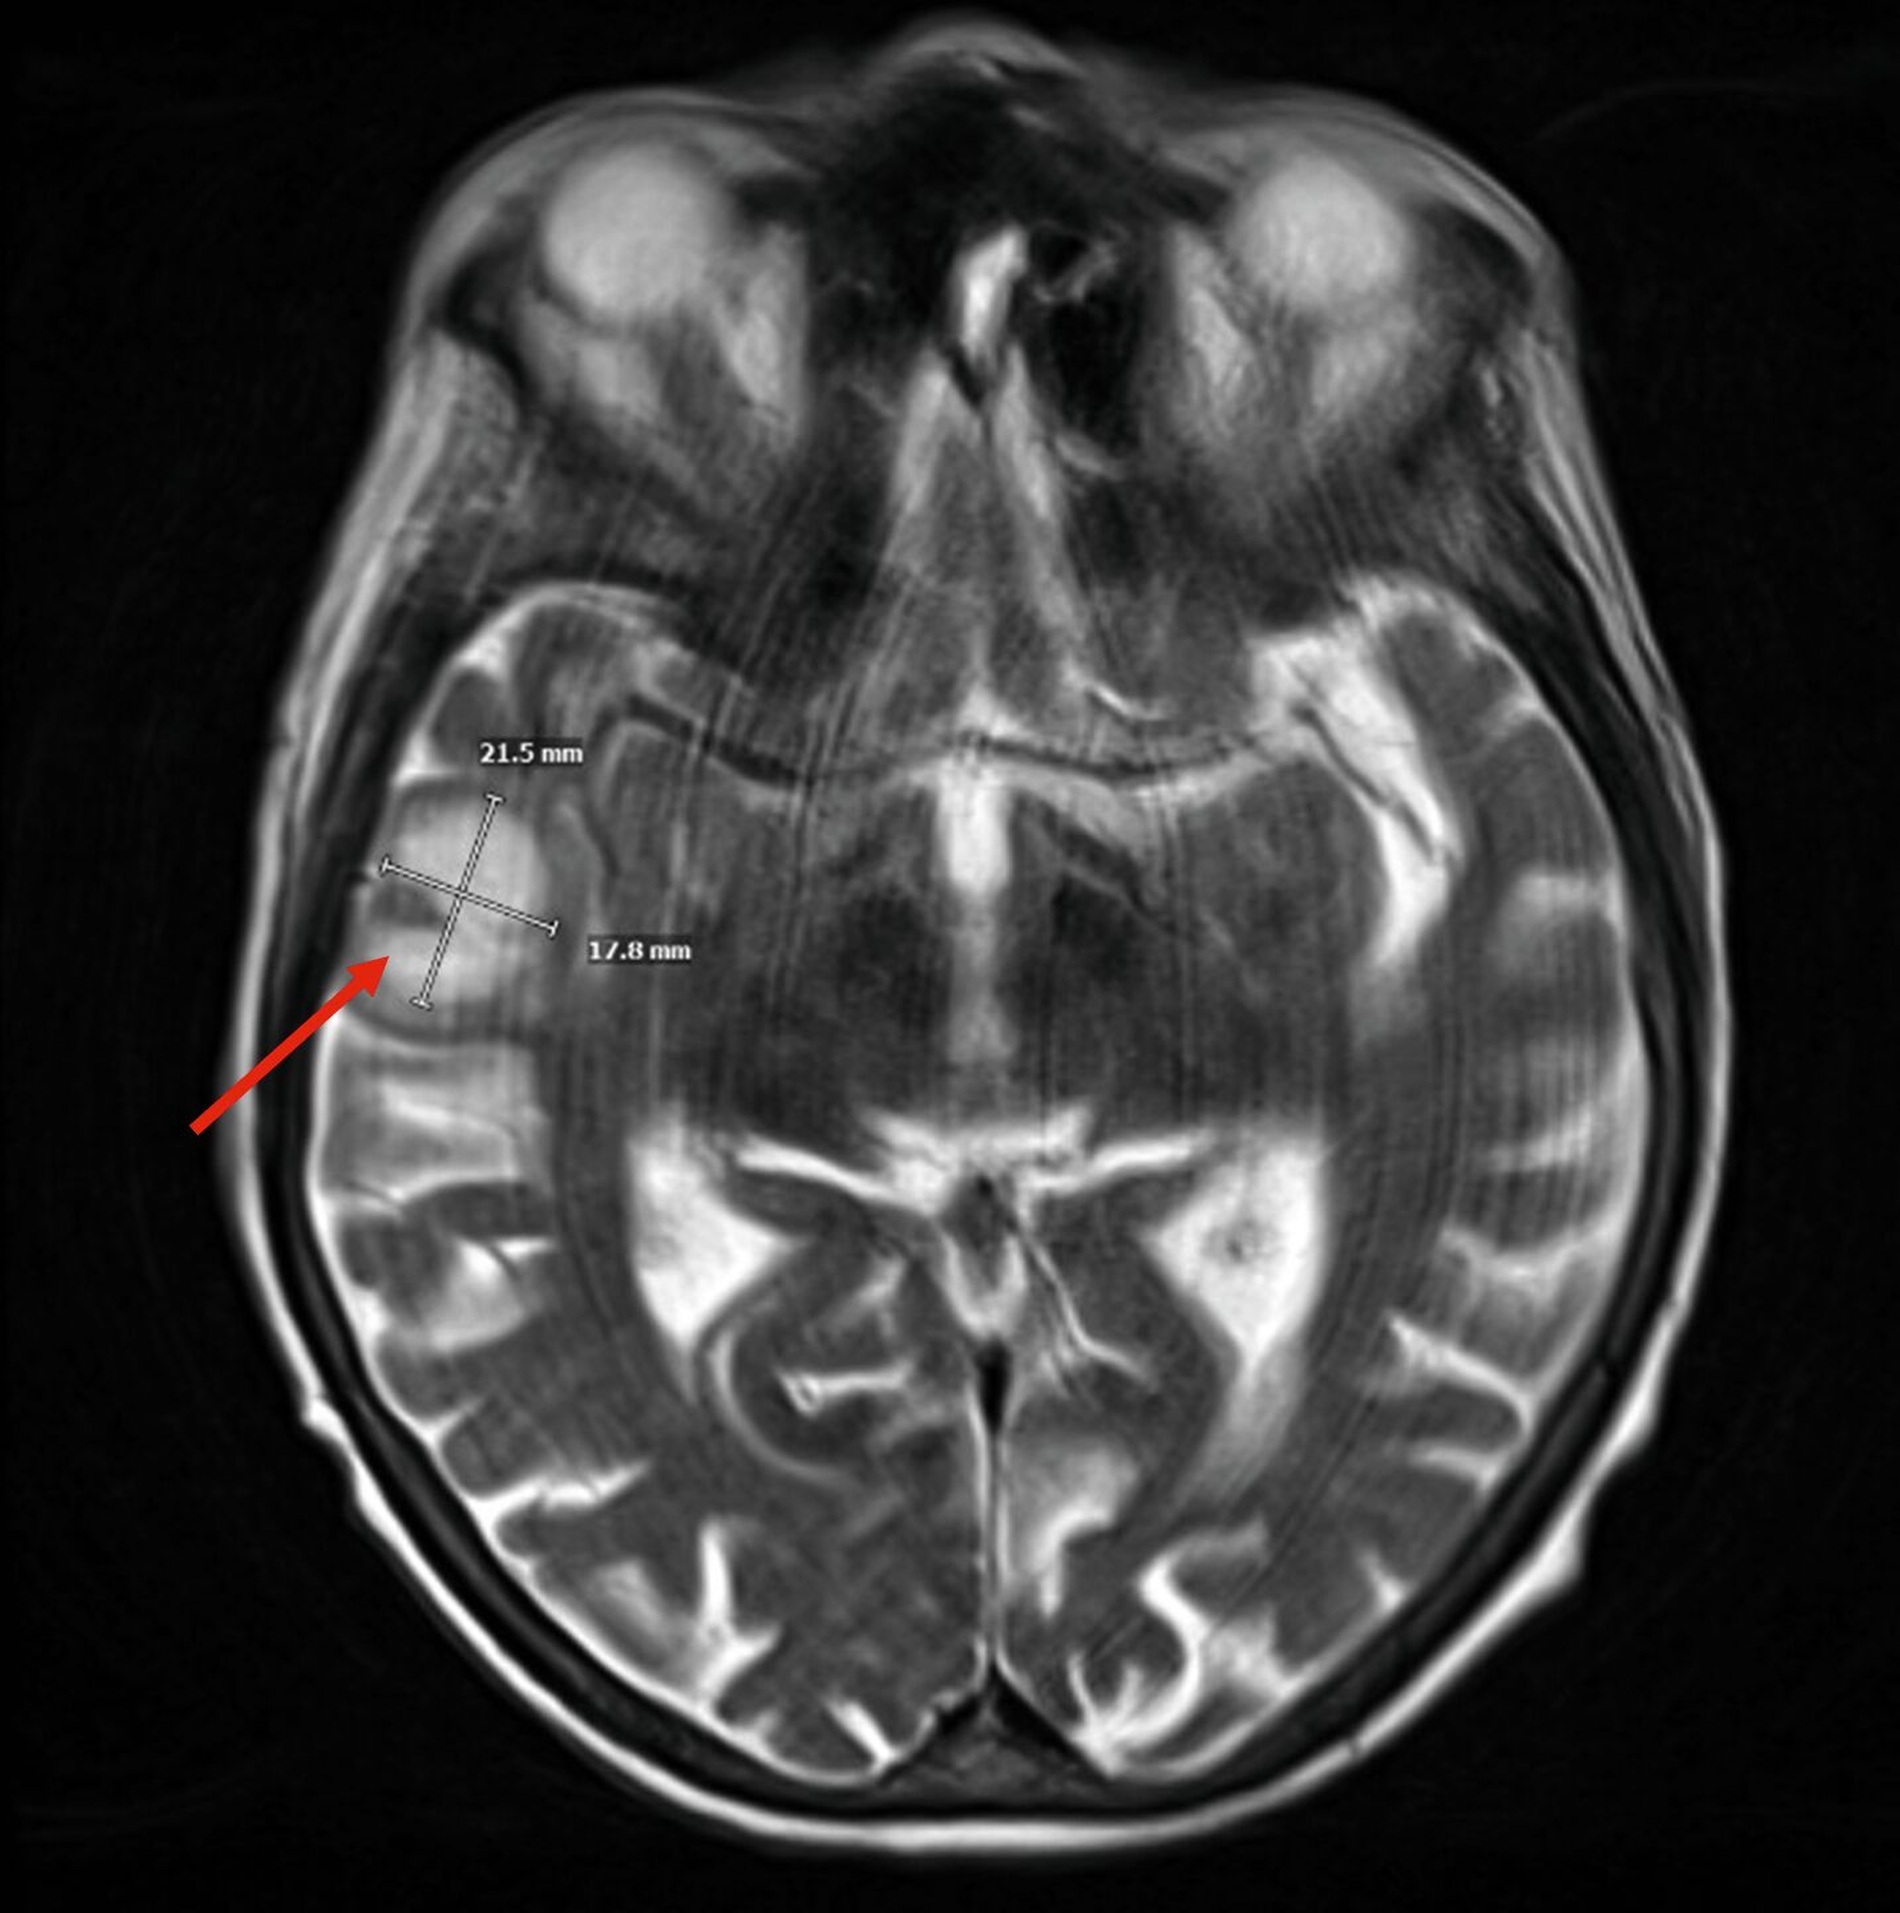

Im weiteren stationären Verlauf fiel am neunten postoperativen Tag eine zunehmende Somnolenz mit Wortfindungsstörungen und Wesensveränderung auf. Die zerebrale Schnittbildgebung zeigte eine hyperintense Läsion temporal rechts mit Verdacht auf einen zerebralen Abszess sowie eine Verschattung im Sinus sphenoidalis (Abbildung 3). Am selben Tag erfolgte durch die Kollegen der Neurochirurgie eine osteoplastische Kraniotomie mit Drainage des Hirnabszesses sowie eine Drainage des Keilbeinsinus durch die Kollegen der HNO (Abbildung 4). In beiden Lokalisationen wurde erneut Streptococcus intermedius als dominierende Bakterienspezies identifiziert – mit Resistenz gegenüber Clindamycin, jedoch guter Empfindlichkeit gegenüber Ampicillin.